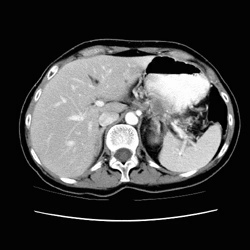

RADIOLOGY: PANCREAS: Case# 123: PANCREATIC CA, VASCULAR ENCASEMENT. 54 year old female with pancreatic mass on outside CT. There is a heterogeneously enhancing, low attenuation, solid mass involving the body and tail of the pancreas. The mass comlpletely encases the splenic artery to its origin at the celiac axis. The celiac axis itself appears encases by the mass and nodal metastases. The origin of the SMA is also encased by nodal metastases. A cystic lesion within the tail of the pancreas most likely represents a pseudocyst secondary to pancreatic duct obstruction by the mass. The mass abuts the posterior gastric wall with possible invasion. By CT, this mass appears unresectable (due to the amount of vascular encasement). This almost uniformly fatal cancer is the 4th most common malignant tumor accounting for 5% of cancer deaths in the United States. Symptoms are usually nonspecific and insidious such that the cancer is advanced by the time of diagnosis. Most cancers occur in the head of the pancreas and are usually adenocarcinomas arising from ductal cells. The sensitivity of CT scan in diagnosing pancreatic carcinoma is approximately 95% whereas that of ultrasound is less than 80% for cancer of the head and 40% for the tail. The primary finding on CT is a focal mass;however, if no mass is present, other findings may suggest neoplasm. First, the pancreas may become more heterogeneous in density with age. Thus, a focal region of homogeneous soft tissue density might raise suspicion of a carcinoma. The presence of both a dilated common bile duct and a dilated main pancreatic duct in the absence of calculus suggests ampullary or pancreatic head neoplasm, but this may also be seen in benign disease. The finding of a dilated main pancreatic duct in the body or tail but not in the head or neck suggests neoplasm, and finally, the finding of rounded convex borders of both anterior and posterior surfaces of the uncinate process raises suspicion for carcinoma. Ten to fifteen percent of patients will have potentially resectable tumors, and they may be distinguished by CT findings. Signs of potential resectability include an isolated pancreatic mass with or without dilatation of the bile and pancreatic ducts and combined bile-pancreatic duct dilatation without an identifiable pancreatic mass. Extension of the tumor beyond the margins of the pancreas, involvement of adjacent organs or the SMA, liver metastases, ascites, and regional adenopathy are signs of unresectability. Unfortunately, most of those who undergo resection eventually die of pancreatic cancer.